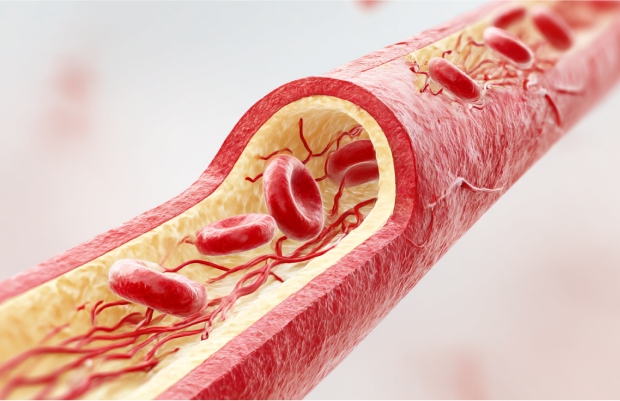

歯周病菌やその毒素、炎症性物質は、単なる「お口の中の問題」にとどまりません。

血流を通して全身へ影響を及ぼし、多様な疾患と密接につながっています。

心臓・脳の病気への影響

歯周病菌が血液に入り、血管で炎症を起こすことで、動脈硬化や血栓の原因になります。その結果、心筋梗塞や脳梗塞などのリスクが高まります。